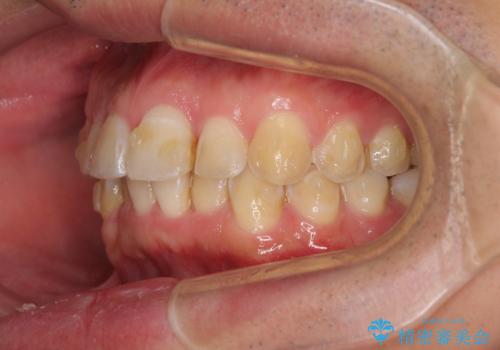

ディープバイトと叢生を解消 インビザライン矯正

- 前歯のデコボコを強い咬みしめを気にして来院された患者様です。

インビザラインを用いて、前歯の叢生を解消するとともに、ディープバイトを改善していくこととしました。

ディープバイトが改善されたことで、顎への負担が軽減され、更には上顎前歯の突出感も改善することができました。

矯正治療後には欠けてしまった修復物をセラミックインレーにて修復治療しました。